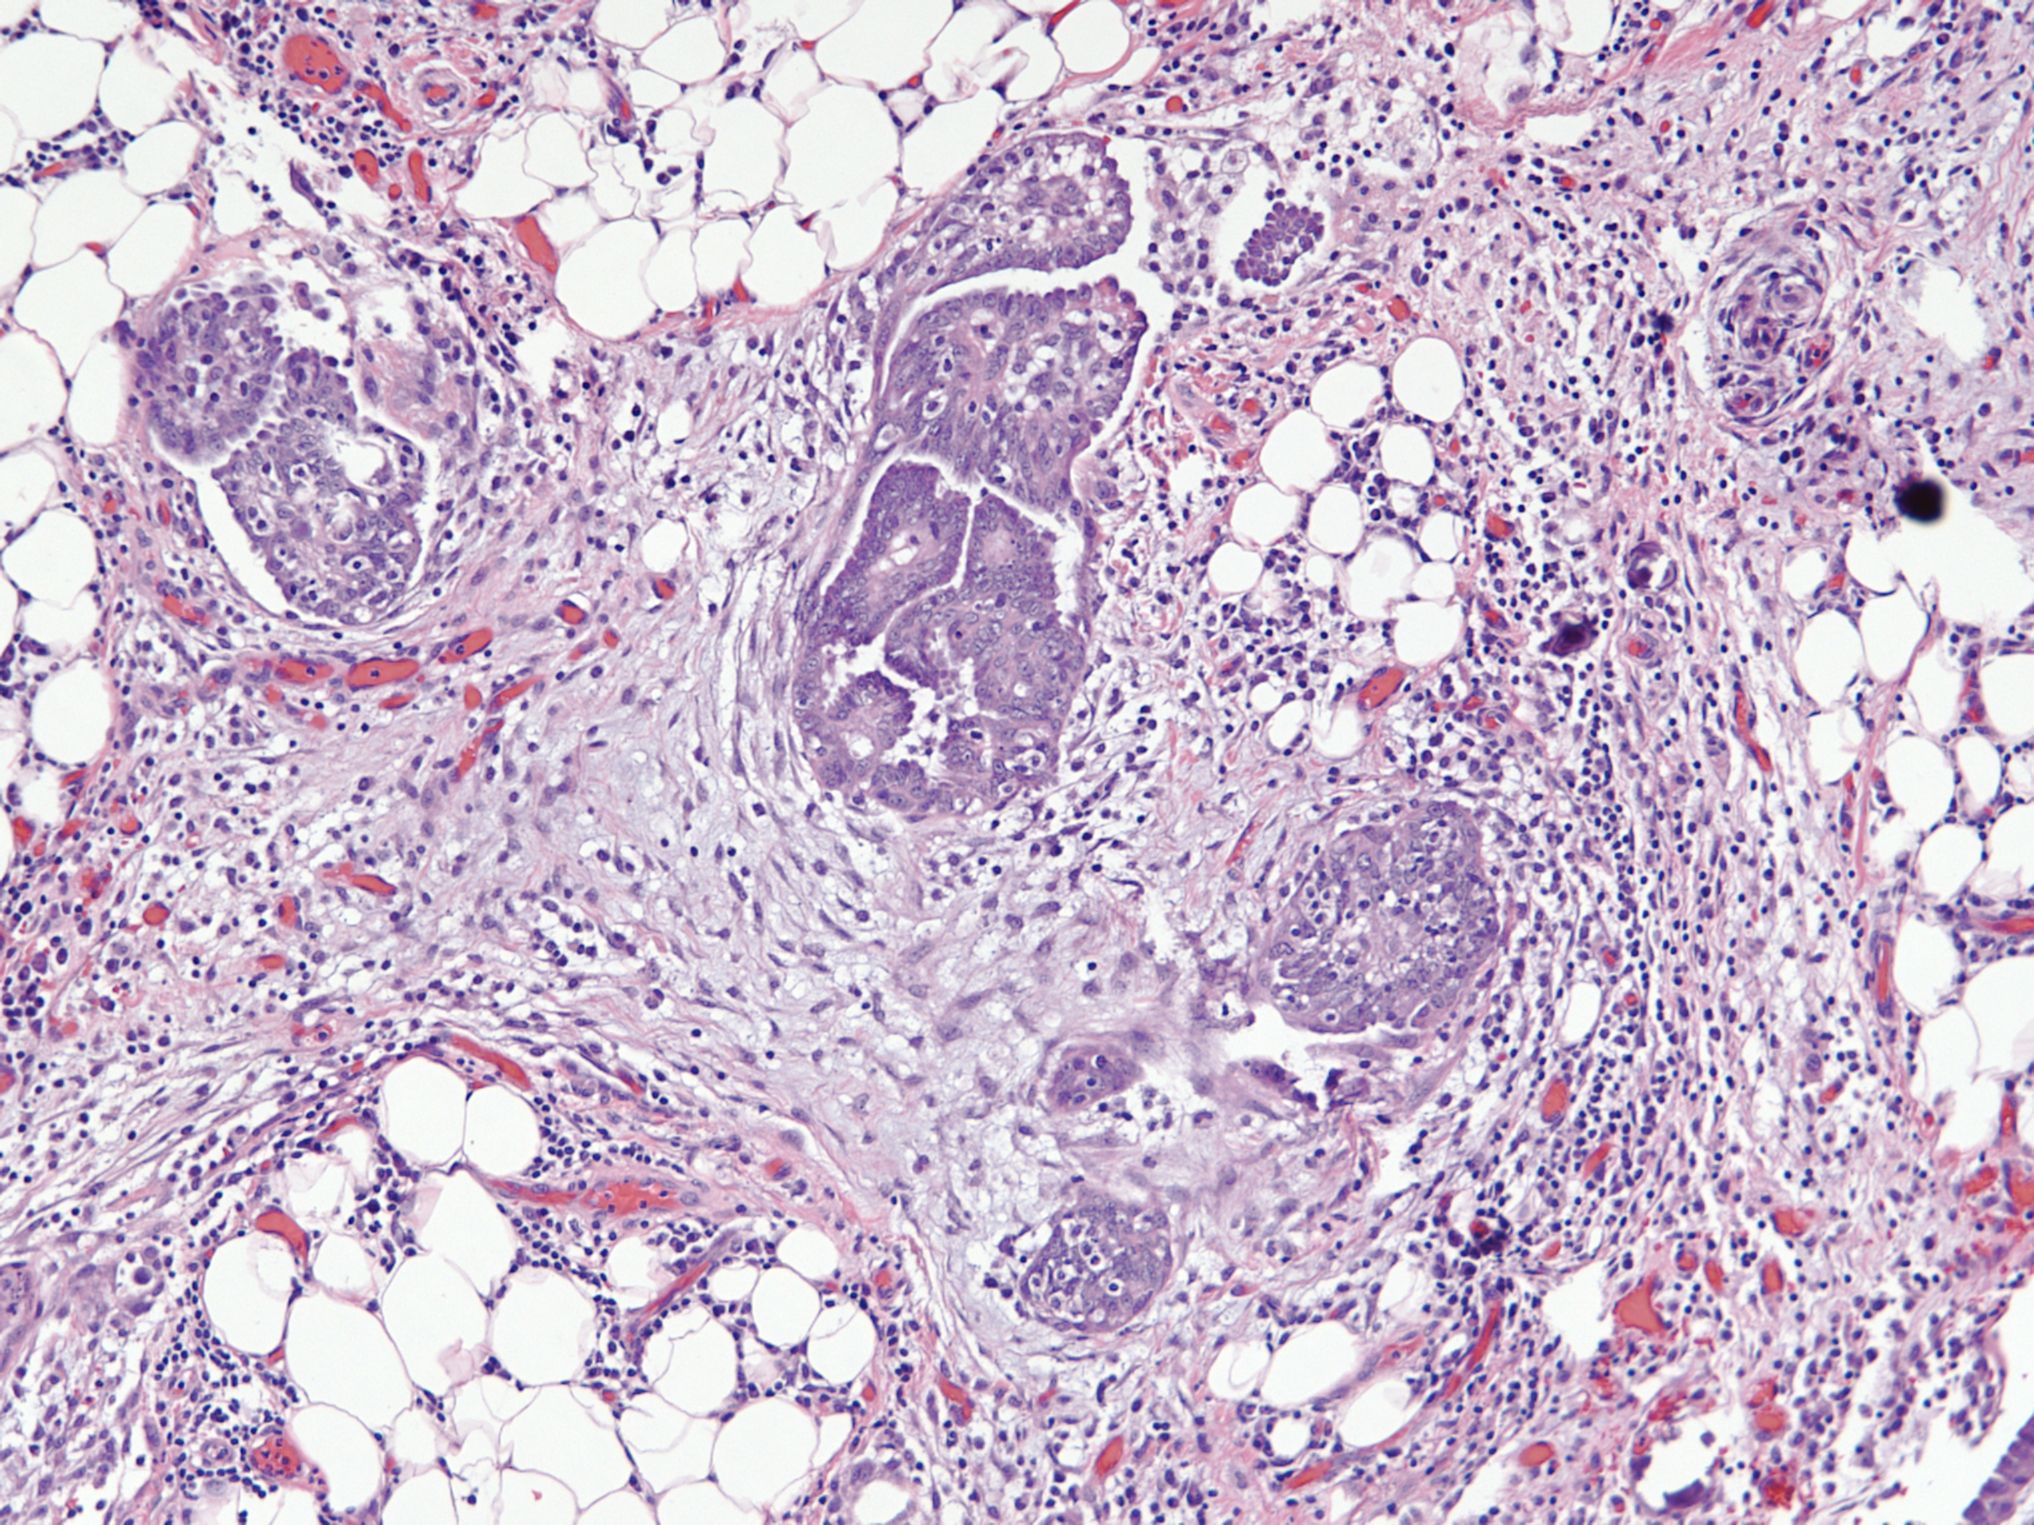

Microscopic (histologic) description

- Uniform / homogeneous population of small cells with scant cytoplasm

- Mild to moderate nuclear atypia at most (grade 1 or 2)

- No nuclear pleomorphism (< 3x variation in size) (Hum Pathol 2005;36:1049)

- May have a conspicuous nucleolus

- Low mitotic index: < 12 mitotic figures per 10 high power fields

- Little to no necrosis

- Psammoma bodies are frequent

- 2 patterns, noninvasive and invasive:

- Noninvasive: nonhierarchical architecture with micropapillary or cribriform patterns with significant expansile growth

- Invasive (> 5 mm): micropapillary or complex papillae, compact cell nests, inverted macropapillae (with broad fibrovascular cores), cribriform, glandular or cystic, solid sheets with slit-like spaces and single cells

- Multiple different invasive patterns can exist within one tumor

Microscopic (histologic) images